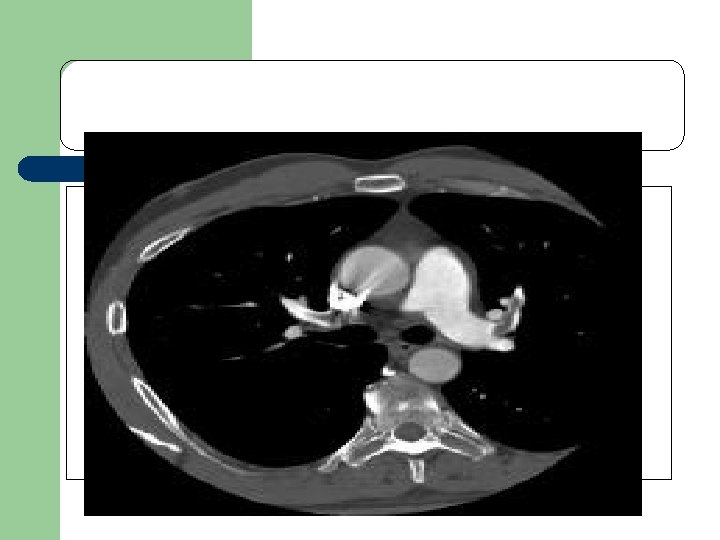

Obstructive shock l l Obstruction to the outflow due to impaired cardiac filling and excessive after load Cardiac tamponade and constrictive pericarditis impair diastolic filling of the Rt. ventricle Tension pneumothorax limit Rt. ventricular filing by obstruction of venous return Massive pulmonary embolism increase Rt. ventricular afterload

l l l Hemodynamic profile in obst. Shock Cardiac output low Afterload high Lt. Vent. filling pressure variable Pulsus paradoxicus in Tamponade Distended Jugular viens